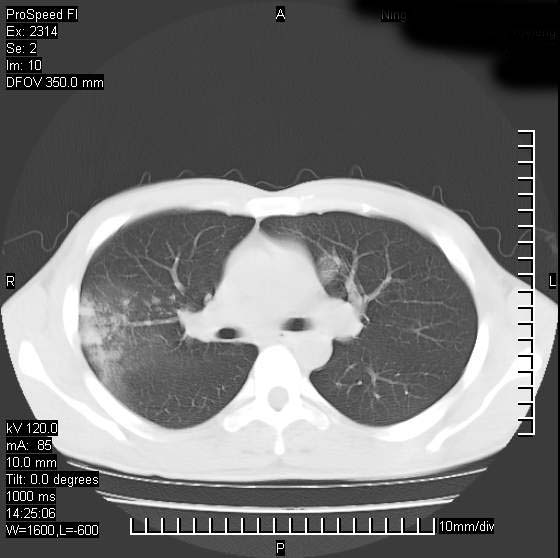

男性,再生障碍性贫血,入院前发热10天,最高40c,右侧胸痛,外院ct示右上,中肺边缘模糊的球性影(就是我现在图中标示的范围),考虑炎症,在我院使用头孢呋辛,洛美沙星10天,高烧消退,自感下午稍有发热,但今天ct示右上,中肺病灶明显扩大,还是考虑炎症,看其中的球型影是否霉菌感染??,是否能排除结核?

肺脓肿,伴双肺播散

片状高密度影内见空洞影,内可见球形软组织密度影,并有新月征,考虑霉菌感染.